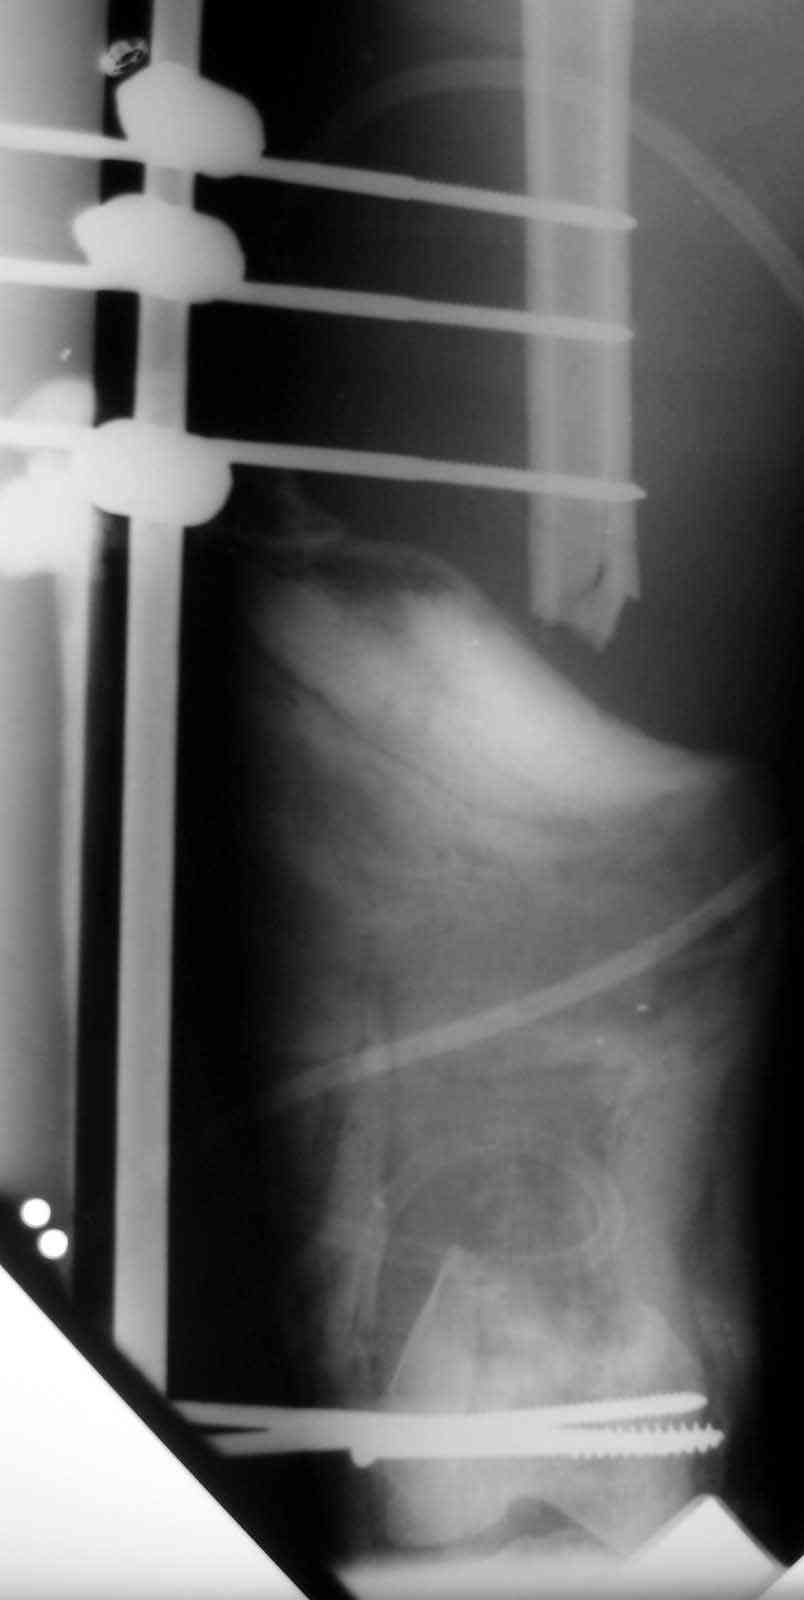

In this particular case, notice the change of fixator - orthofix type of unilateral fixator worked well initially but did not allow me to compress beyond a point, which is when I changed to an ilizarov for further compression at the gap/nonunion site.

I have done both for this problem and I feel Ilizarov bone trnapsort is the

best[ probably only ]answer. Vasc fib graft in the femur especially in this

regeon has a problem ie; inadequate fixation distal fragment and long period

to hypertrophy.

With Ilizarov you need a mid shaft corticotomy and trnasport. The frame

needs to extended down to the tibia with hinges across the knee